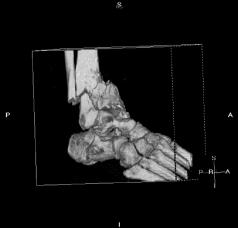

Pre-skin graft & bone infuse surgery X-Rays of the left ankle

These x-rays were taken just prior to surgery where grafts of skin (from Liam's own leg) were used to cover the open wound on Liam's left

ankle. Dr. Gottlieb also took the initiative to infuse material into the tibia gaps (shown in the front ankle view). The infused bone material

should fill in the existing bone gaps and fuse the various bone fragments, resulting in a much stronger support structure. It is hoped that the

3 cm fragment (shown in the side view) will fuse with the other tibia bones as time progresses. No immediate plan exist to modify the remaining

bone fragments / configuration.